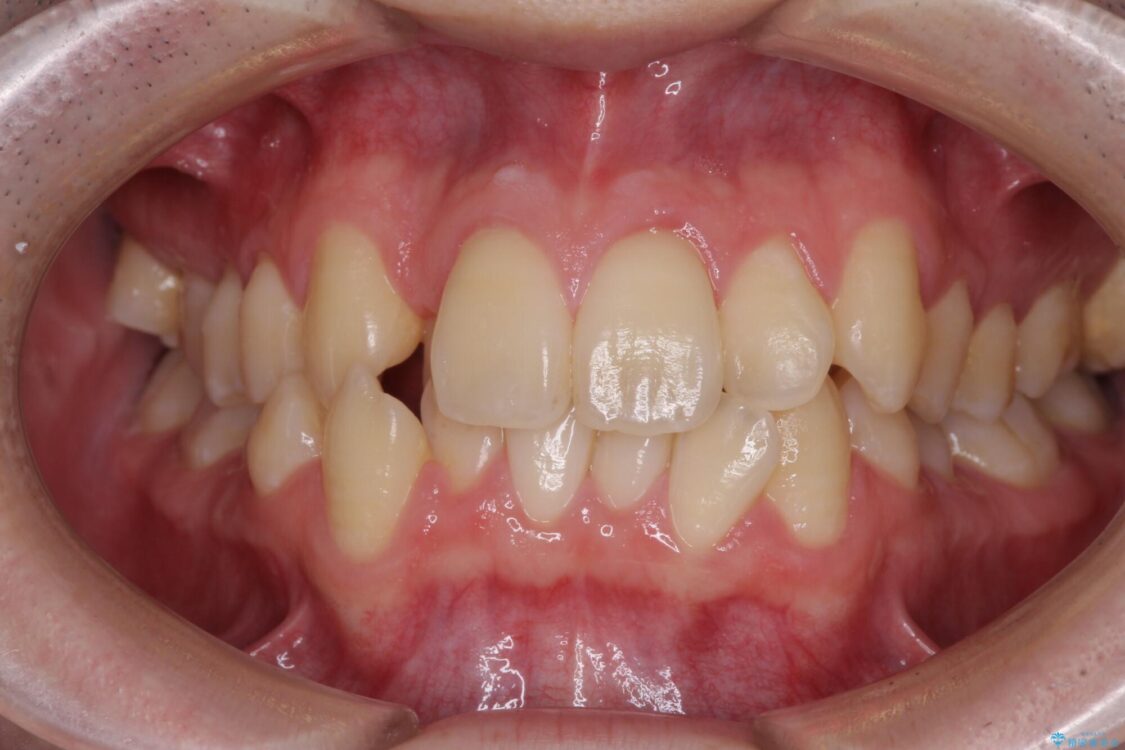

八重歯や奥歯の噛みにくさを気にして来院された患者様です。

前歯のクロスバイトや八重歯の他に、左右最後臼歯のシザーズバイト(鋏状咬合)が認められました。

治療後

• 全顎的なクロスバイト 補助装置を用いてワイヤー矯正 治療後画像